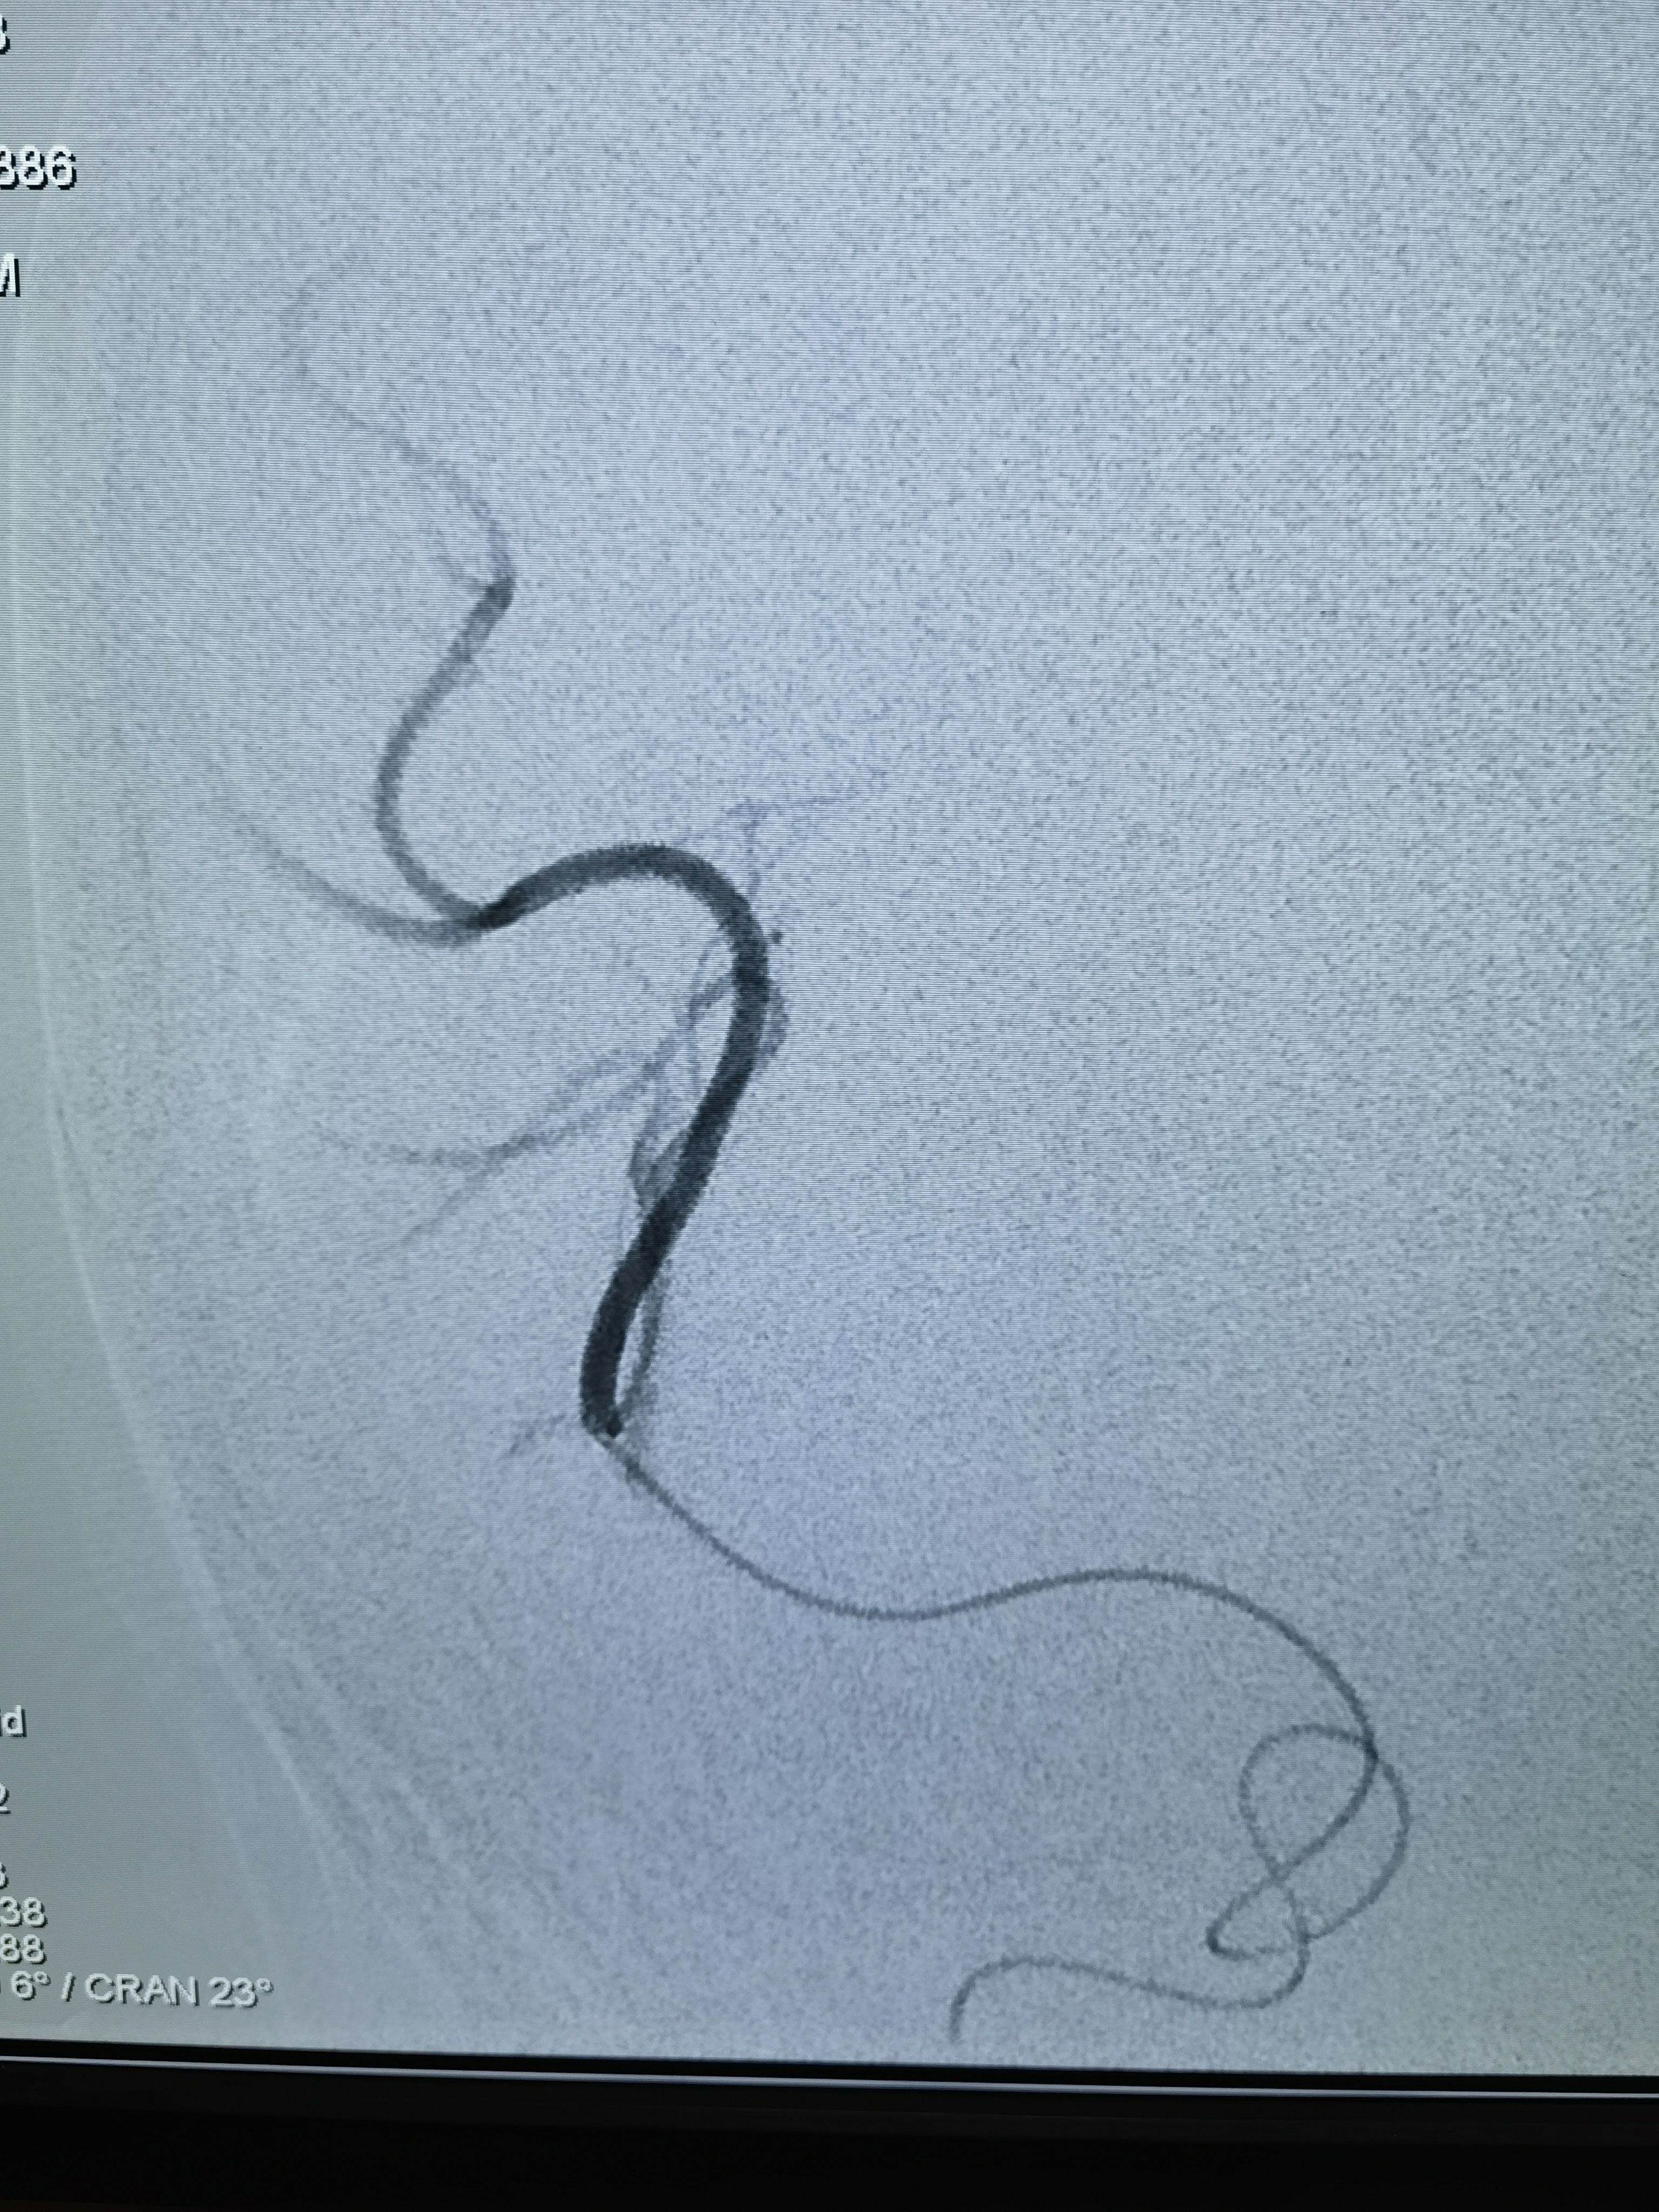

改为右桡动脉入路,桡动脉搏动也弱,考虑大动脉炎可能右上肢血管也受影响了,不过还是穿刺成功,泥鳅导丝带猪尾巴管造影,在腋动脉处通过困难,试了两次还是顺利过去了,弓造影上可以看到右侧锁骨下动脉几乎不显影,肋颈干发出粗大分支血管向右上肢供血,说明锁骨下要么闭塞,要么也是重度狭窄,弓造影结束长泥鳅导丝保留,退出猪尾巴管,交换上SIM造影导管,在弓里成袢后超选右颈总困难,导管被血管抱死,导管软,内衬泥鳅导丝推不动!

换MPD头端放到头臂干右颈总开口处,内衬猪尾巴管,利用猪尾巴管头端的弯儿勾右颈总动脉,猪尾短,截了一节MPD,把泥鳅导丝头端送到右侧颈内动脉,猪尾巴管带到分叉,猪尾巴管造影确认右侧大脑中动脉闭塞!

闭塞血管明确,需要取栓治疗。问题来了!手头没有合适的6F经桡的中间导管,也没有合适的6F长鞘!怎么办?换8F鞘!鞘头进入血管一点,能固定住就行,泥鳅长单弯同轴带8F禾木的导引导管到右侧颈内动脉!